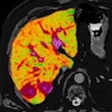

Perspectum MRI software helps guide liver surgeries